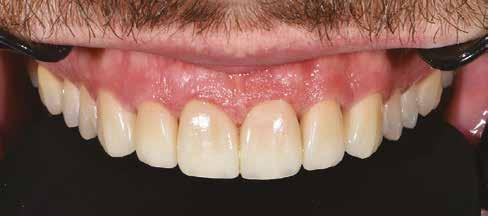

Az oxigén inhibíciós réteg kialakulásának elkerülése érdekében a kerámiafelszíneket glicerin géllel (Liquid Strip, Ivoclar Vivadent, Schaan, Liechtenstein) borítottuk, majd ezeket a felszíneket ismét 20-20 másodpercen keresztül világítottuk. A végeredmény megfelelt a páciens esztétikai igényeinek (6. a. ábra). Az átadott restaurátumok épségének megőrzése érdekében, a páciens számára éjszakai fogvédő sín készült. Az ötéves kontroll alkalmával megállapítottuk, hogy az elvégzett kezelésünk továbbra is sikeresnek tekinthető (6. b. ábra)

A páciens elégedett volt a végleges restaurátumok színével, formájával és méretével. A kezelés végeredménye kielégítette az esztétikai elvárásait (9. ábra). A frissen átadott restaurátumok épségének megőrzése érdekében a páciens számára éjszakai fogvédősínt készítettünk. A páciensünk a négyéves kontrollvizsgálat során is nagyon elégedett volt a kezelés eredményével. A korábban meglévő fekete háromszögek eltűnésének különösképpen örült (9. és 10. ábrák)

A páciens teljesen elégedett volt a kezelések befejezését követően elért esztétikai végeredménnyel (9. ábra). A terápiás erőfeszítéseink eredményeinek köszönhetően újra képes felszabadultan nevetni és mosolyogni. A cikkben bemutatásra kerülő eset jól példázza a multidiszciplináris beavatkozások alkalmazásában rejlő előnyöket. A megfelelő sorrendben végzett orthodonciai és restauratív kezelésekkel lehetővé vált a páciens mosolyának minimálinvazív módszerekkel történő optimalizálása. A körültekintő tervezésnek köszönhetően nem került sor felesleges beavatkozások elvégzésére, és emiatt a kezelések befejezéséhez szükséges idő sem nyúlt a szükségesnél hosszabbra. Arra is felhívnánk a figyelmet, hogy a jól megszervezett, továbbá a lehető legkevesebb rendelési időt felhasználó kezelések – a beavatkozásokat végző fogorvosok számára is – rendkívül kedvezőek lehetnek.